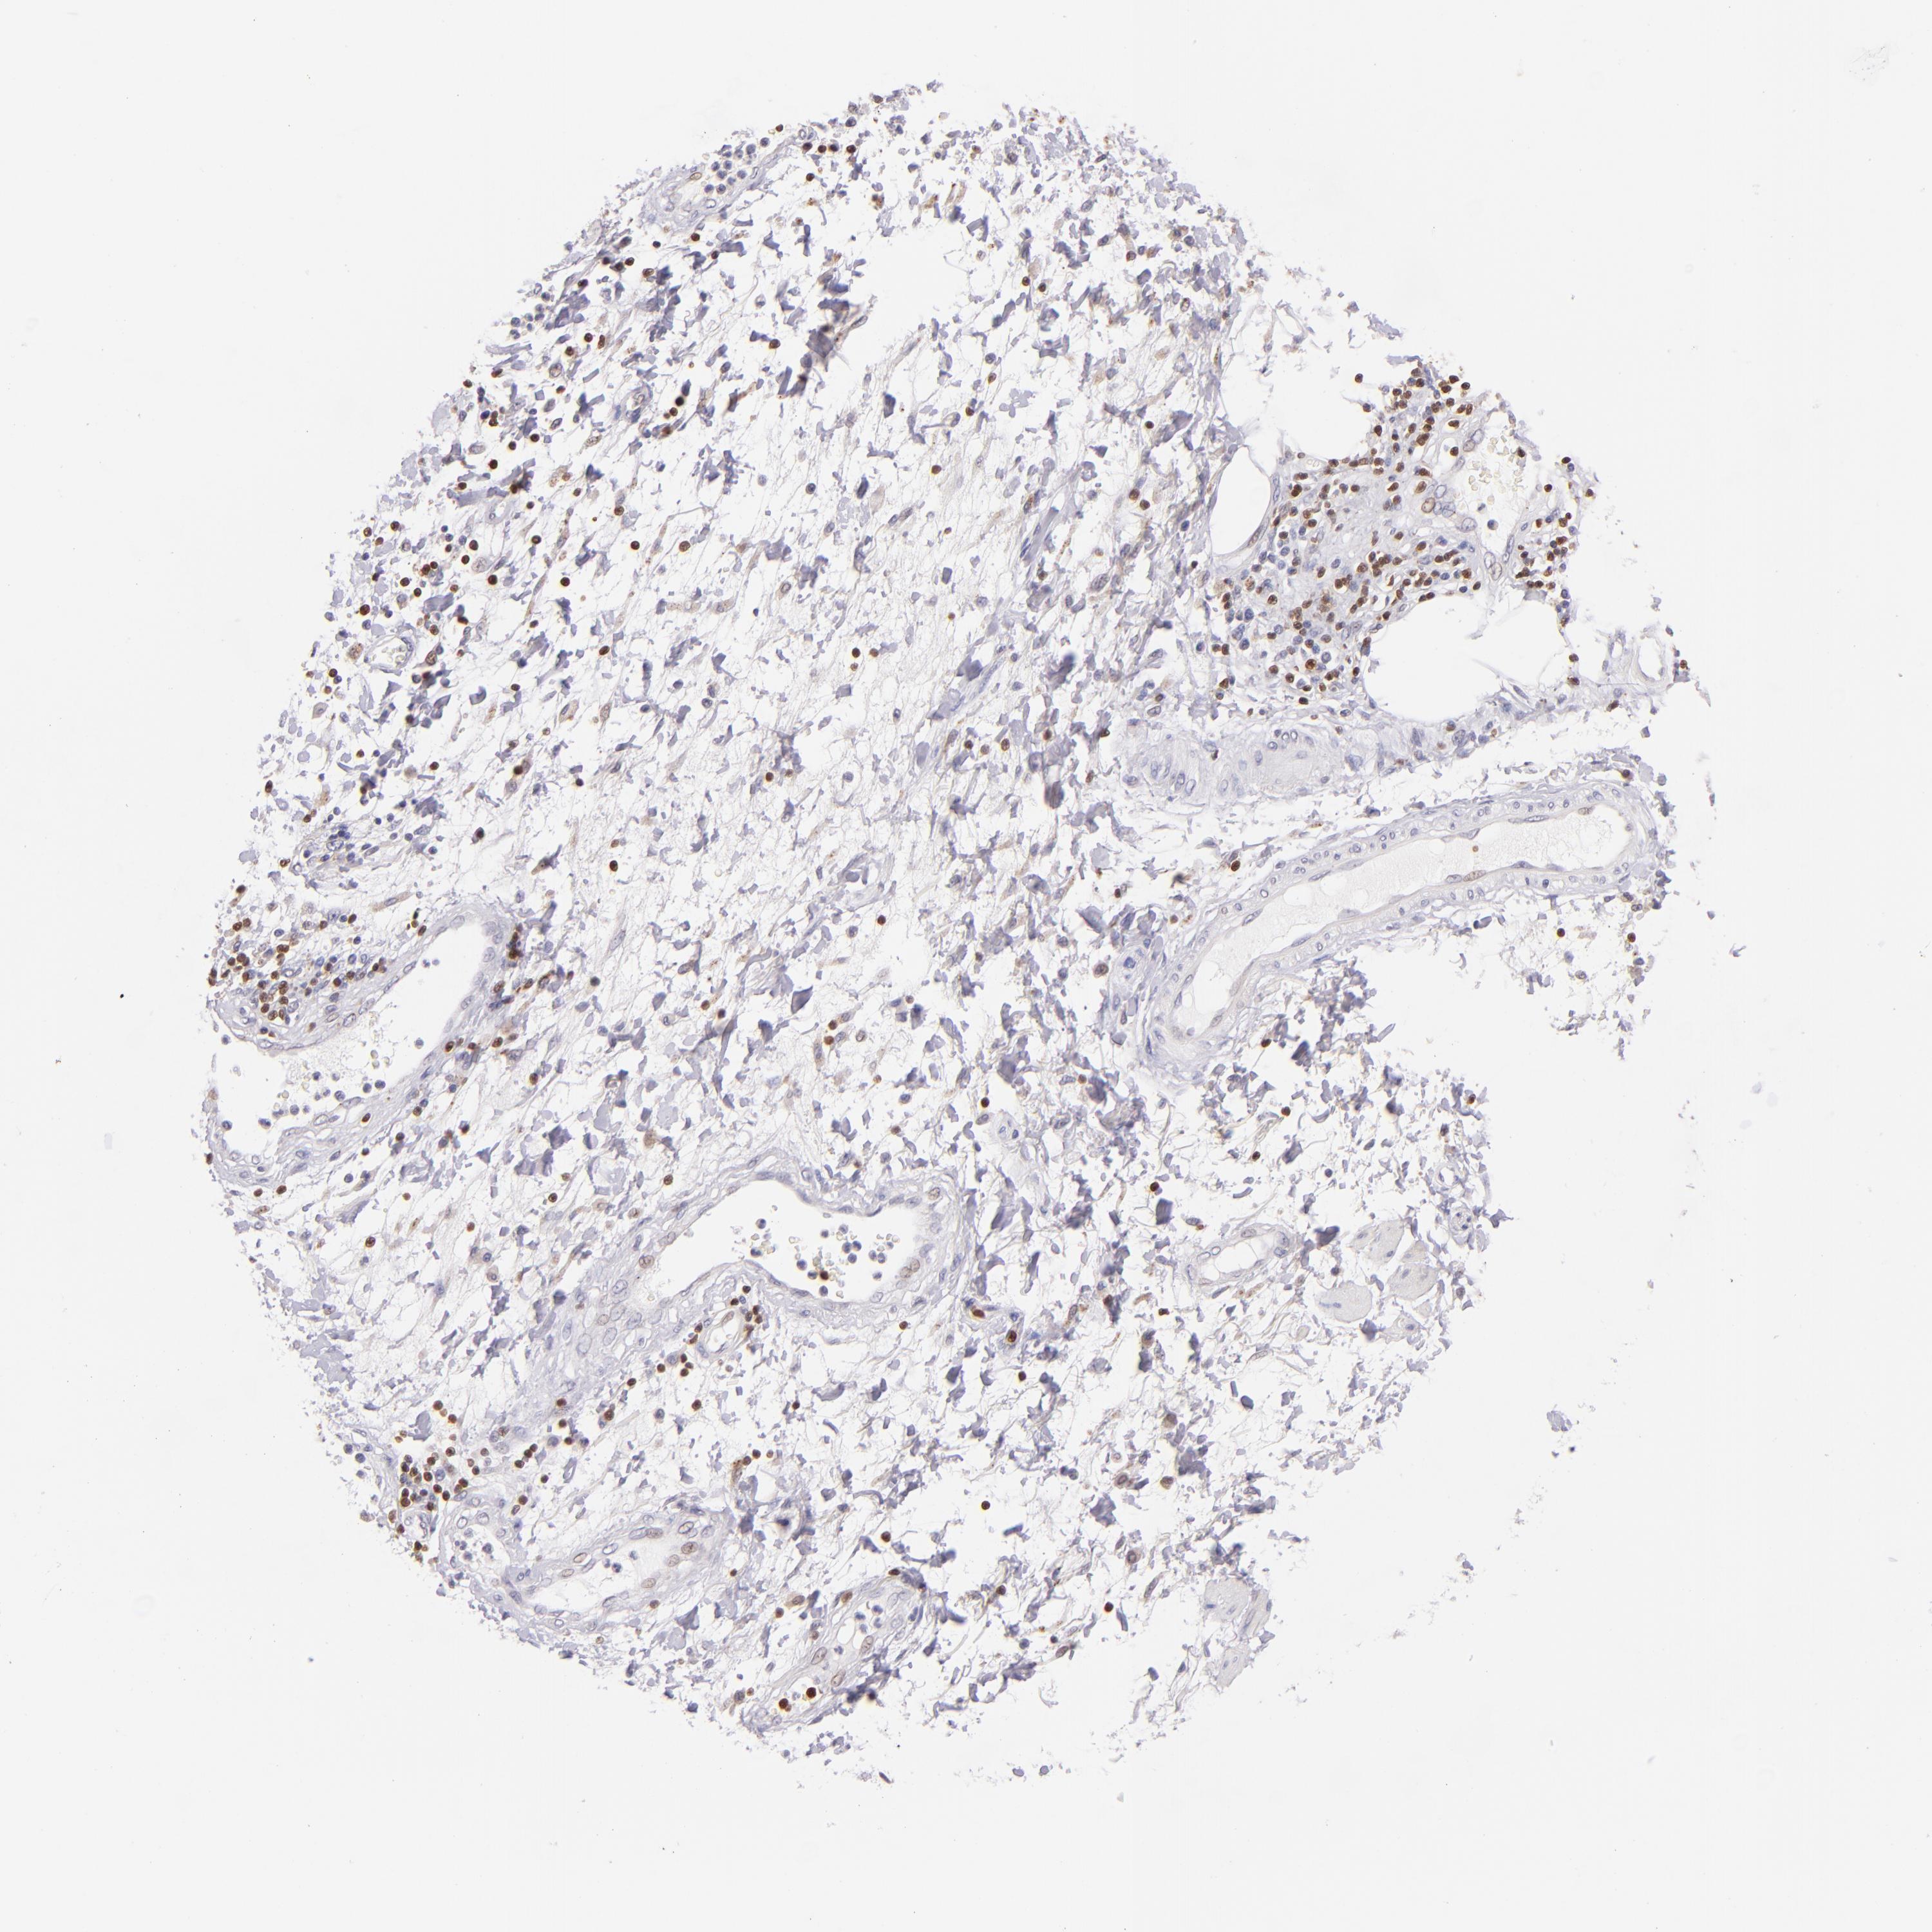

STOMACH CANCER - Protein expressioni

A mouse-over function shows sample information and annotation data. Click on an image to view it in a full screen mode. Samples can be filtered based on level of antibody staining by selecting one or several of the following categories: high, medium, low and not detected. The assay and annotation is described here.

Antibody stainingi

Antibody staining in the annotated cell types in the current human tissue is reported as not detected, low, medium, or high, based on conventional immunohistochemistry profiling in selected tissues. This score is based on the combination of the staining intensity and fraction of stained cells.

Each image is clickable and will lead to virtual microscopy that enables deeper exploration of all samples and also displays staining intensity scores, fraction scores and subcellular localization as well as patient and tissue information for each sample.

Antibody HPA003134

Antibody CAB002625

Staining

High

Medium

Low

Not detected

Intensity

Strong

Moderate

Weak

Negative

Quantity

>75%

75%-25%

<25%

None

Location

Nuclear

Cytoplasmic/membranous

Cytoplasmic/membranous,nuclear

Adenocarcinoma, NOS